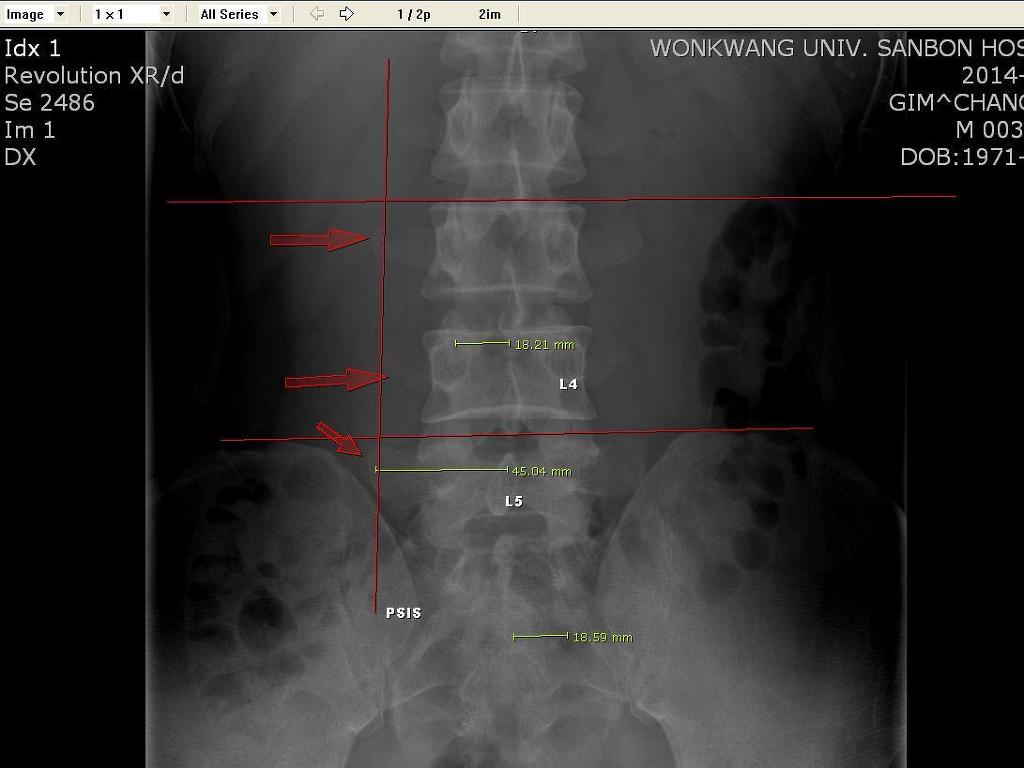

첫번째 선은 늑골하부 선입니다. -  랜드마크로 L2-3를 찾을때 씁니다. 근데 그어보니 약간 위쪽이네요...보통 이런식으로 L2-3를 찾습니다. L3 TP는 침도에서는 중요시하는 부위입니다. 신수지실 라인이죠.... 보시면 아시겠지만 L4보다 오히려 L3 TP가 더 큽니다...힘을 더받아서 그렇다는 침도하는 쪽에서 그렇게 말합니다. 그래서 중요하다고 하죠... QL 치료 포인트입니다. 머 침도하는 쪽은 중측 근막이라고 하던데...궁금하시면 찾아보시면 될듯.

두번째 선은 다들 아시다 시피 장골능입니다. 보통 L4 spinal process 위를 지나거나 L4-5사이를 지나갑니다. 장골능에도 피부지방층이 있어서 그으면 보통 L4 spine이 잡힙니다.

세번째 세로선은 PSIS 수직선입니다. 제가 보통 transverse process위치를 정할때 PSIS수직선을 잡습니다. 거리가 4.5cm 정도 보통사람은 됩니다.

그리고 후관절은 엄지손가락 하나 넓이인 2cm 가량 외측에 위치합니다. - 후관절 바로 외측으로 회선근과 다열근이 붙으므로 주요 치료부위입니다. 4~5cm로 뼈에 닿게 찍어주시면 자극이 될겁니다. 화타 협척혈이죠..더 붙여서 놓여서 5~6cm 자침하면 황색인대 자침됩니다.... 침도로 하면 갈고리 침으로 찢어줘야겠죠...협착증에...효과 좋지만 조심해야겠죠...

PSIS에서 수직선을 그으면 L3,4.5 TP tip 부위입니다. L4,5번은 4번의 경우 하부에 장요인대, 5번은 측면에 장요인대가 붙습니다. 요부 불안정성 원인의 가장 큰 원인인 장요인대 치료 포인트 입니다. 그리고 L5 TP에서 장골능쪽으로 밀어 넣어주면 장요인대 장골부착부까지 치료할수 있을겁니다. 침만 놓아도 효과는 좋지만 프롤로로 하면 더 좋겠죠... 정확히 TP에 침을 라인에 맞게 놓으면 찍을수 있으니 찍고 살살 주변을 긁어주시면 안전히 자침가능합니다. 머 깊이 놔도 별 문제 없지만요...6*4가 적당합니다. 장골쪽은 더 길어도 될듯합니다.

맨아래 수평선은 서서찍었다는 가정하에 골두 위치를 보고 다리길이를 봅니다. 이사람은 다리길이가 다르네요... 정확이 서있지 않아 그런경우가 많으므로 다시 찍어볼 필요가 있겠습니다. 다리길이가 짝짝이라서 위에 장골능 높이도 다르네요...그래서 좌측 이 전체적으로 높아져있습니다.